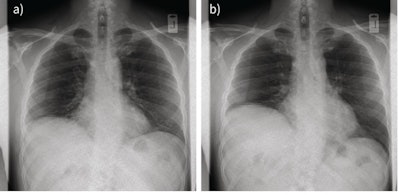

The researchers observed paradoxical motion (in which the diaphragm moves in the opposite direction than it should during inhaling and exhaling) in 14 patients, and they confirmed it in six who also underwent fluoroscopy or ultrasound. In four patients, dynamic chest radiography showed reduced hemidiaphragm excursion, but no paradoxical motion. In three patients, the researchers observed normal diaphragm motion.